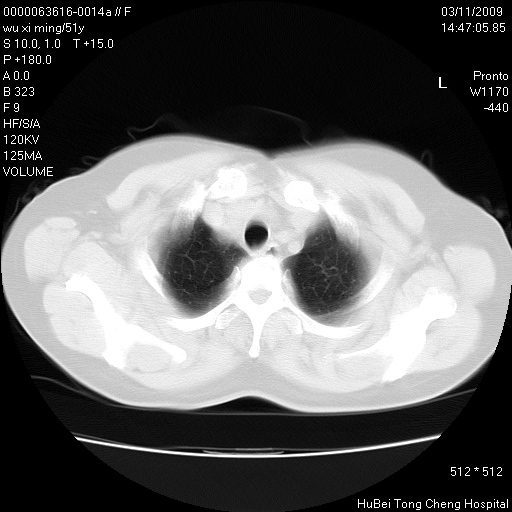

患者 女,51岁。因“胆囊炎,胆囊结石”,行常规术前胸部x线检查发现:右上肺结节病灶,建议行进一步检查。患者无咳嗽、咳痰及咯血等呼吸道症状,近期出现背部疼痛不适。

胸部ct轴位平扫(层厚10mm,螺距1.5,重建间隔10mm;部分层面:层厚3mm,螺距1.0,重建间隔3mm),图像如下:

右肺周围型肺癌伴肺内转移信胸椎转移

1、周围型肺癌。(毛刺正、血管束集征,分叶。)

集束征,胸膜牽拉征,毛刺,淺分葉高度提示ca.

右肺周围型肺癌伴肺内转移及胸椎转移。已无手术机会。